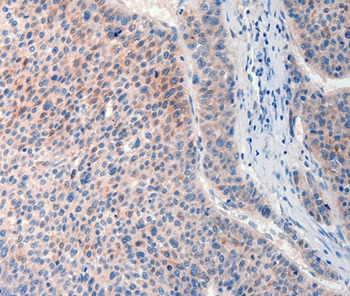

Immunohistochemical analysis of paraffin-embedded Human liver cancer tissue using #37293 at dilution 1/20.

Immunohistochemical analysis of paraffin-embedded Human lung cancer tissue using #37293 at dilution 1/20.